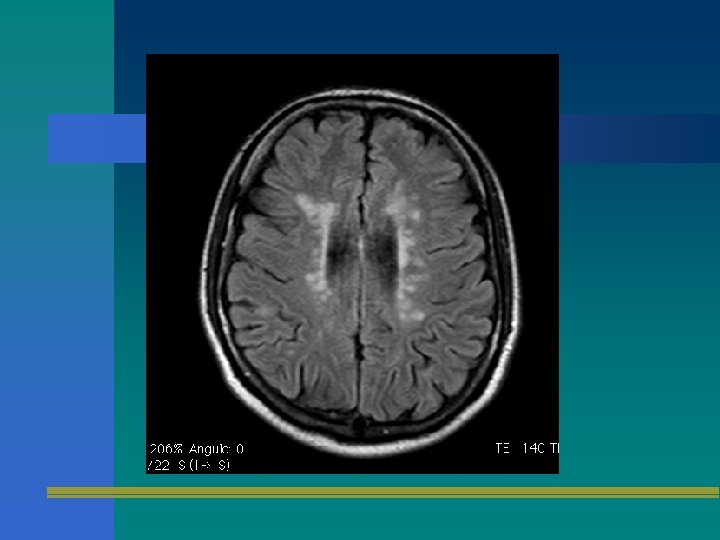

Elementos de apoyo diagnóstico • Resonancia magnética cerebral/espinal • Potenciales evocados – Visuales – Somatosensitivos – Tallo • LCR + Bandas oligoclonales